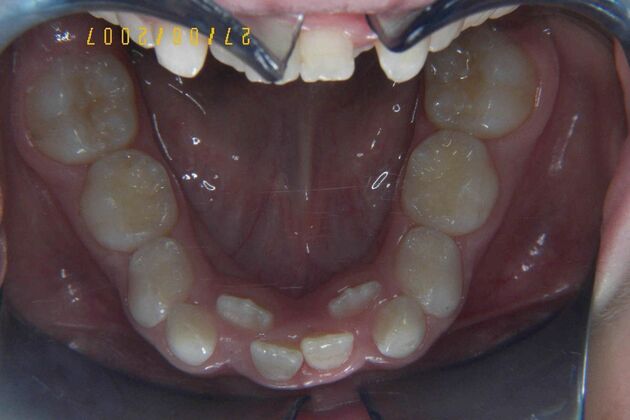

Patient is 9 years old and presents with 100% overbite and blocked out upper and lower lateral incisors. Both upper central incisors are palatally inclined causing a lack of space available for most anterior teeth. Advised her parents that she needs Phase I Interceptive Orthodontic treatment to provide room for all upper and lower front teeth. Phase I treatment was begun and finished, then began Phase II treatment shortly thereafter to finalize case. Removable retainer were fabricated for retention.